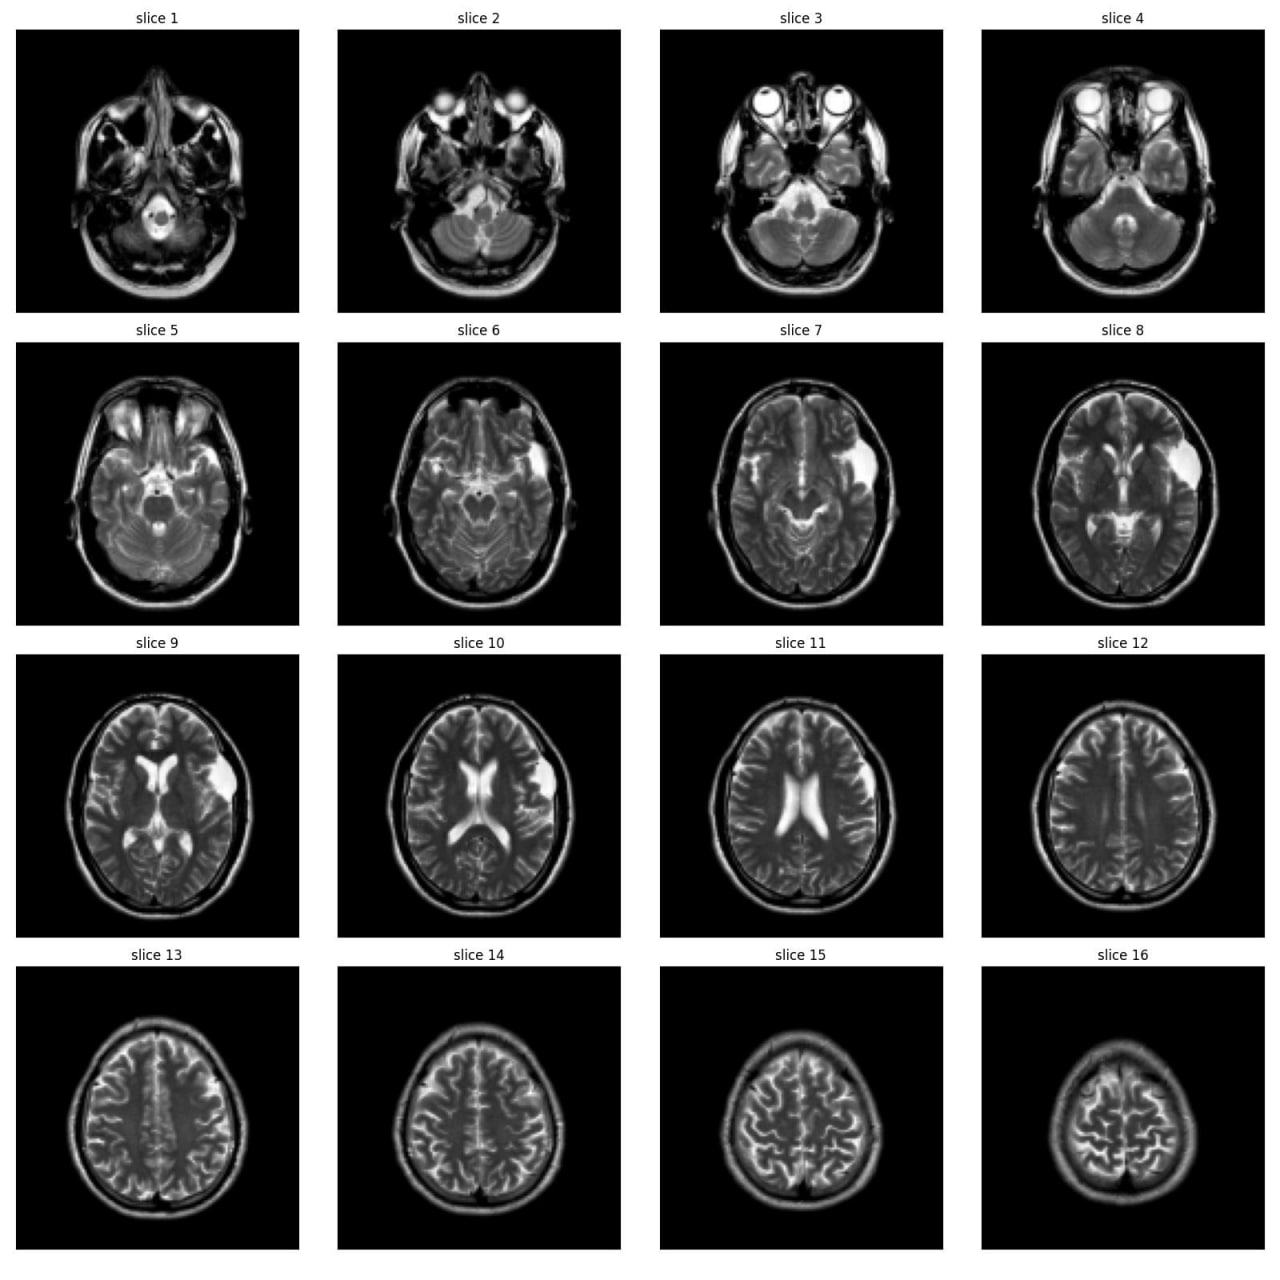

As part of the JIM3 team, I competed in the IAAA competition, which involved a dataset of 4,000 MRI images, with only 500 labeled as abnormal. The competition aimed to develop a model for patient-level abnormality classification. We utilized various models, including EfficientNet, DenseNet, ResNet, custom CNN models, and Vision Transformers (VIT), along with different preprocessing techniques. Working closely with a medical team, we converted subject-level annotations into slice-level annotations for more effective model training. Despite discovering inconsistencies in the test set and normal cases after the competition, we secured 17th place among over 100 teams. The technical team is currently working on a paper using the annotated data from this project.